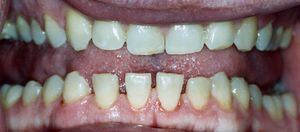

Mandibular overgrowth leads to prognathism, maxillary widening, teeth separation and jaw malocclusion.